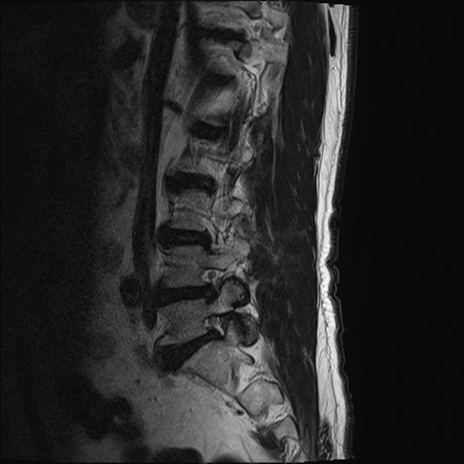

【整形】TIPS症例2 腰椎MRI T2WI(矢状断像)

【症例】70歳代男性

【主訴】左下肢痛

【現病歴】2週間前くらいから腰痛、左下肢痛あり。左臀部から大腿、下腿外側のしびれが常時ある。歩行とともに同部位の痛みあり。

【身体所見】Lasegue70-/60+、Bragard-/±、PTR ±/±、ATR -/-、IP 5/5、TA 5/4、TS 5/5、EHL 右第1足趾なし/3、FHL 5/5、hypersthesia(-)、足背動脈触知良好

異常所見と診断は?